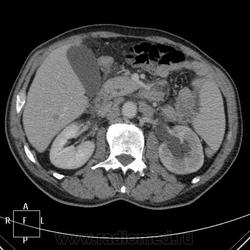

Пациент 71 года, поступил с подозрением на тромбофлебит правой нижней конечности. После УЗИ ОБП (не могу предоставить иллюстрации), переведен в онкологическое отделение с диагнозом мтс печени и забрюшинных лимфоузлов. Рентгенография ОГК, ФЭГДС - без особенностей. Колоноскопия - сигма непроходима аппаратом из-за сдавления извне.

портальная фаза:

Источник мтс-опухоль левой стенки мочевого пузыря?

Однозначно мета в печени, забрюшинные узловые образования, подобные образования в правой подвздошной области, пораженная стенка мчевого пузыря (инфильтративный рост). Левый мочеточник видится тоже измененным(?), гидронефроз слева. Полистать бы сериию, а так складывается впечатление о раке мочевого с mts в регионарные и забрюшинные лимфоузлы, печень...

С уважением, С.Н. Нагорный

Я тоже поставила первичным рак мочевого пузыря. Пациент уехал в областной онкодиспансер.